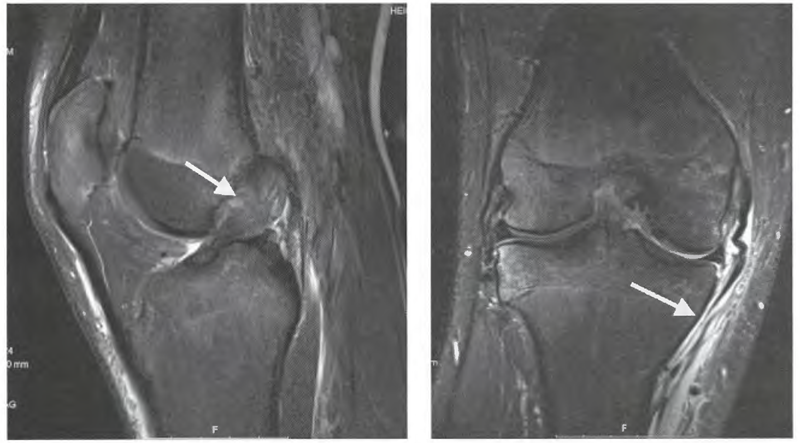

MRI检查可显示膝关节内侧结构损伤的部位及程度,以及是否合并有软骨、半月板及其他韧带的损伤情况,有助于确定MCL撕裂的位置,也能排除stener病变。

图4 MCL损伤的MRI影像

MRI分级:Ⅰ度损伤表现为 MCL局部水肿,纤维轻度撕裂;Ⅱ度损伤表现为 MCL走行区部分断裂伴高信号;Ⅲ度损伤表现为MCL走行区完全断裂并伴有迂曲回缩。